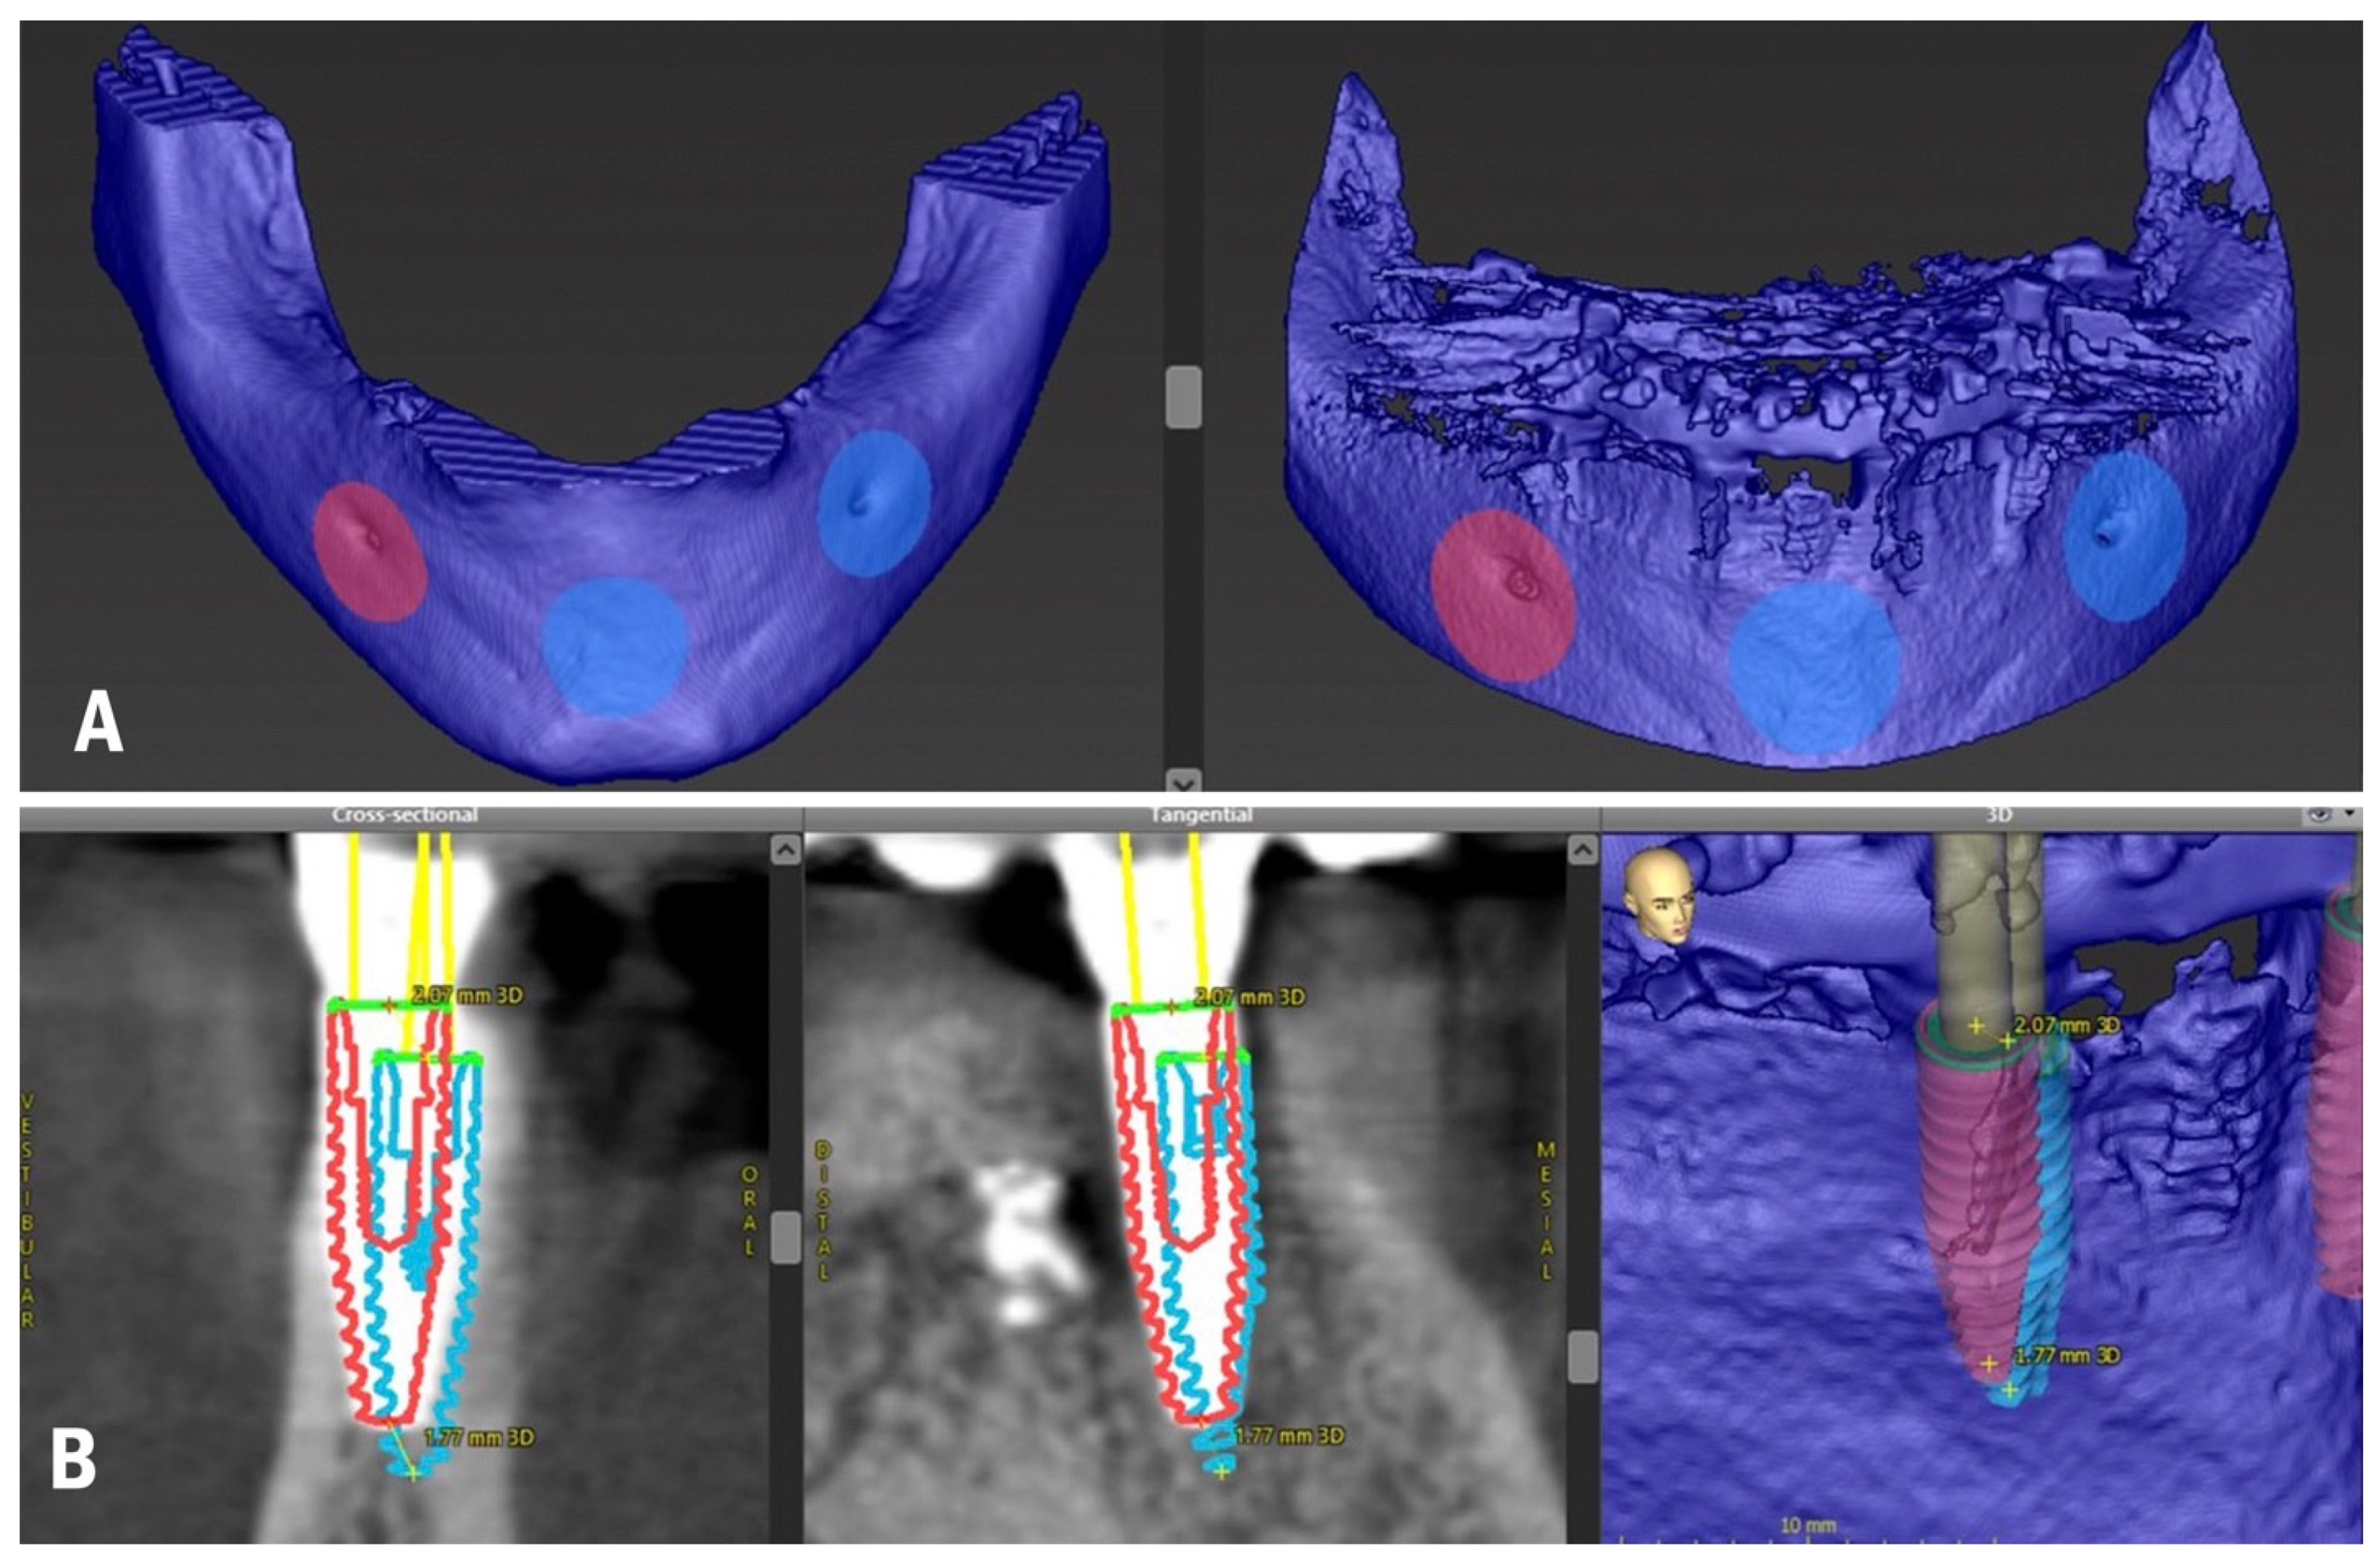

For the in vivo evaluation of the DICOM-to-DICOM matching protocol, the accuracy assessment technique was applied, which consists of evaluating the matching of the planning dataset with the surgery results dataset. The patient received a second CBCT scan after the implant placement and delivery of the final prosthesis to perform an accuracy analysis (Figure 1D). The same CBCT device was used to obtain more qualitative data since the registration accuracy of implant planning software is significantly influenced by the preprocessing of imported data [31]. The area of interest (mandible) was segmented from the CBCT scan, which allowed for more qualitative matching. Data in DICOM format were inserted into the treatment evaluation tool of coDiagnostiX, and the matching of the preoperative and postoperative CBCT scans was performed (Figure 2A).

Figure 2.

(A) Planning and postoperative CBCT matching; (B) Accuracy analysis with postoperative CBCT (blue colour—planned implant position, red colour—actual implant position).

The limitation of the DICOM-to-DICOM protocol might be the discrepancy between the CBCT scans. To minimize this influence, the same CBCT device was used, and matching was performed in multiple areas with clearly visible anatomical structures following the recommended protocol of the treatment evaluation tool. Each implant was aligned in the preoperative and postoperative CBCT, and accuracy values were automatically generated by the software (Figure 2B). The 3D, distal, vestibular, and apical deviations were recorded on the coronal (base) and apical (tip) points of the implants, as well as angular deviations. The results are reported in Table 1.